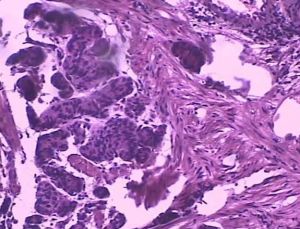

糞便鏡檢發現特徵性的卵囊可確診。需多次糞檢,糞便標本經改良抗酸染色後容易發現卵囊。有時當原蟲處於細胞內期時,只能靠腸組織活檢查才能確診。患貝氏等孢子球蟲病的人,其糞便中常含有由嗜酸性細胞衍化酶夏科-雷登結晶,周圍血常呈現嗜酸性細胞增多症。感染者的腸黏膜活檢可見微絨毛縮短,固有層有淋巴細胞,漿細胞和嗜酸性細胞浸潤。治療